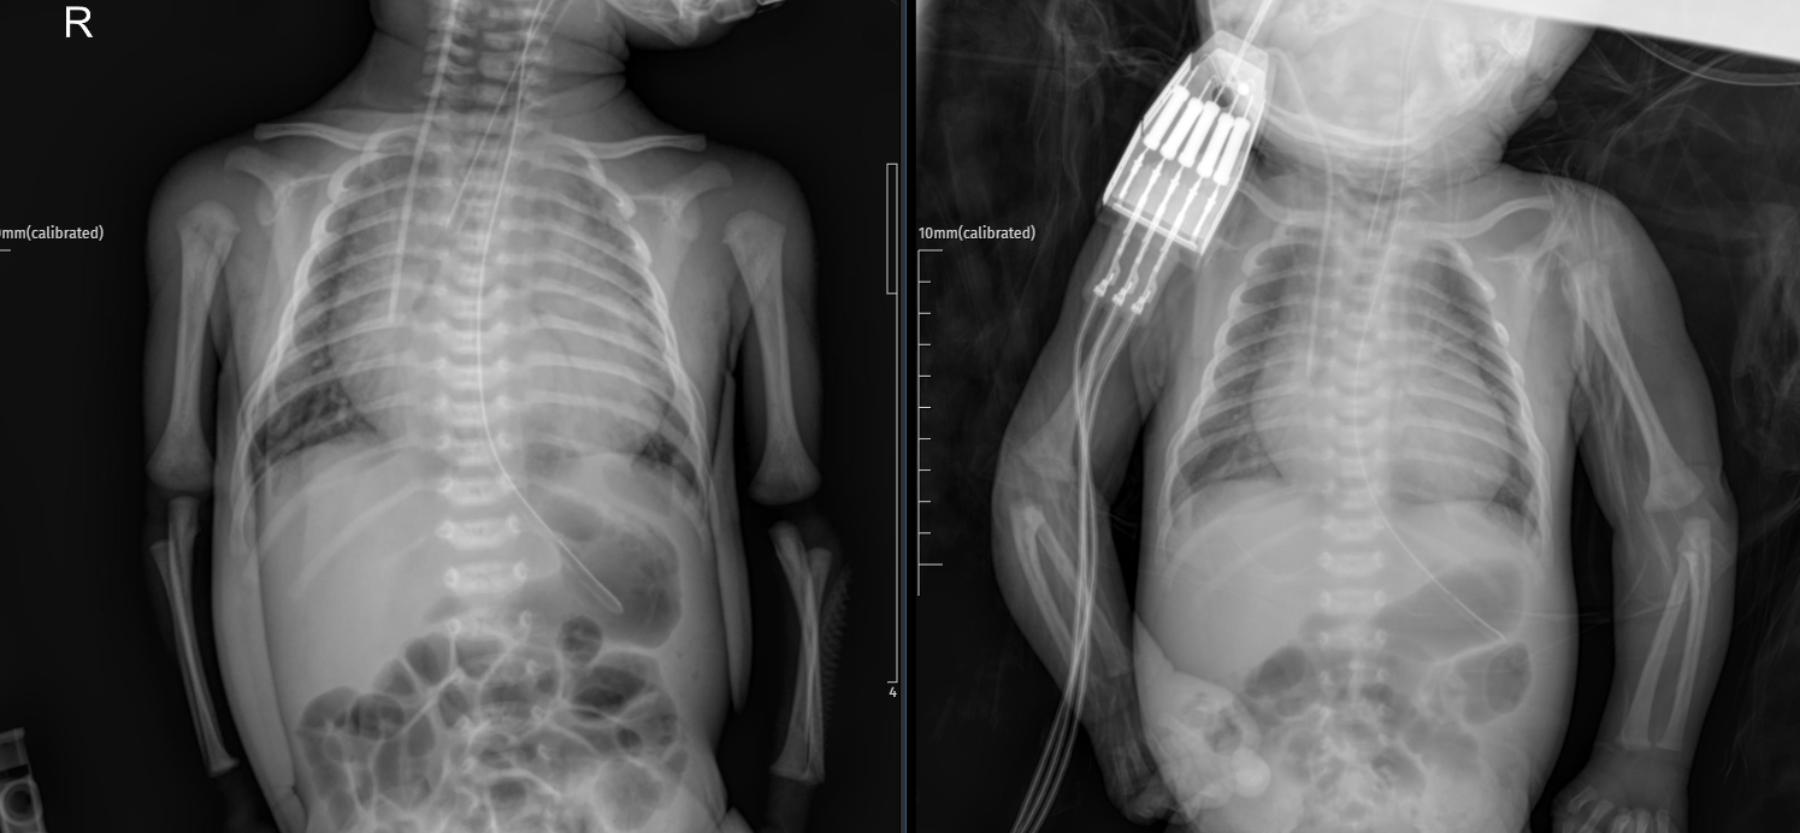

- Left Image (Admission X-ray): A supine anteroposterior chest and abdominal radiograph of a neonate, showing an endotracheal tube in place and a nasogastric tube extending into the stomach. The cardiac silhouette appears enlarged with an increased cardiothoracic index. The lung fields show mild vascular congestion.

- Right Image (ICU Day 2 X-ray): A follow-up supine anteroposterior chest and abdominal radiograph, showing similar findings with the endotracheal tube and nasogastric tube in position. The cardiac silhouette remains enlarged. There is evidence of an intravenous line stabilizer on the right arm.

Upon arrival at the emergency department, a PA chest X-ray was performed.

- PA Chest X-ray Interpretation (Left Image): The chest X-ray showed an increased cardiothoracic index, indicative of cardiomegaly. This finding prompted an urgent consultation with pediatric cardiology.